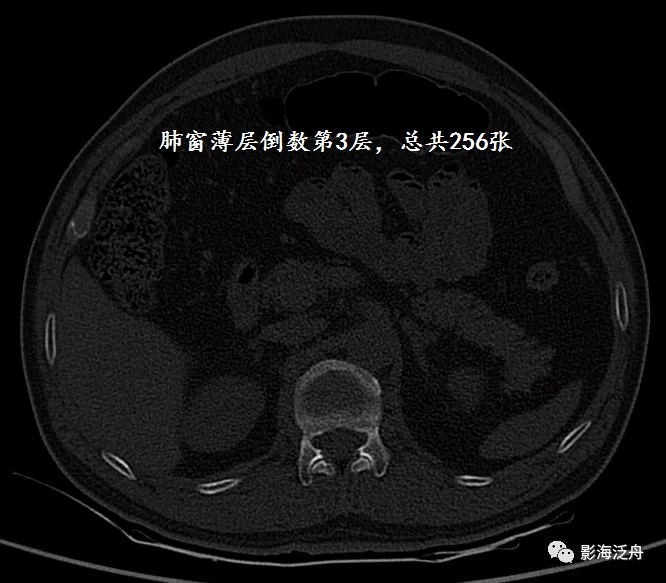

病例一:女 , 48岁 , 摔伤致腰背部疼痛、活动受限2天。

这个病例是非常特殊的 , 患者外伤史明确 , 但整体观察下来并没有看到明确的骨折征象 , 回过头反复阅片才在薄层胸部CT最后两个层面观察到椎体的细微骨折征象 , 而其余层面都是正常的 。 这样的病例 , 对于一些阅片习惯不好的朋友 , 漏诊率几乎是百分之百的 。 因为大部分阅片者往往不能较为均匀地去观察一组影像图片 , 总是会在一组图像刚开始和快要结束的时候不由自主地加快鼠标的滚动速度 , 一不小心就错过了重要的内容 。 所以 , 如果你也有类似的习惯 , 那就要当心了!